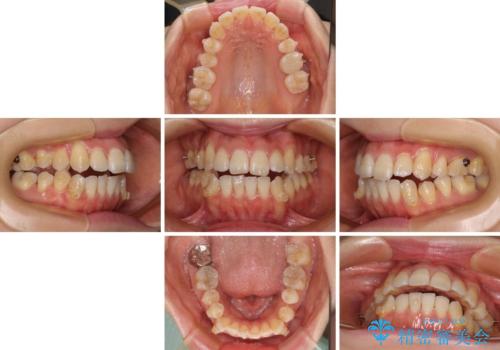

八重歯と開咬の抜歯矯正 ワイヤー装置を併用したインビザライン矯正治療

- 矯正装置

- インビザライン・審美装置

- 治療期間

- 1年10ヶ月

開咬の改善にはインビザラインが有効であり、インビザライン単体での治療を検討しましたが、上顎前突を回避するために上顎左側第一小臼歯抜歯を行うこととしたため、補助装置とワイヤー矯正を併用した上で、インビザラインによる矯正治療を行うこととしました。

インビザライン矯正治療では、臼歯の圧下による前歯部の早期接触が大きな問題となっています。開咬では、その臼歯圧下を逆手にとって前歯部の非接触を改善させることができます。